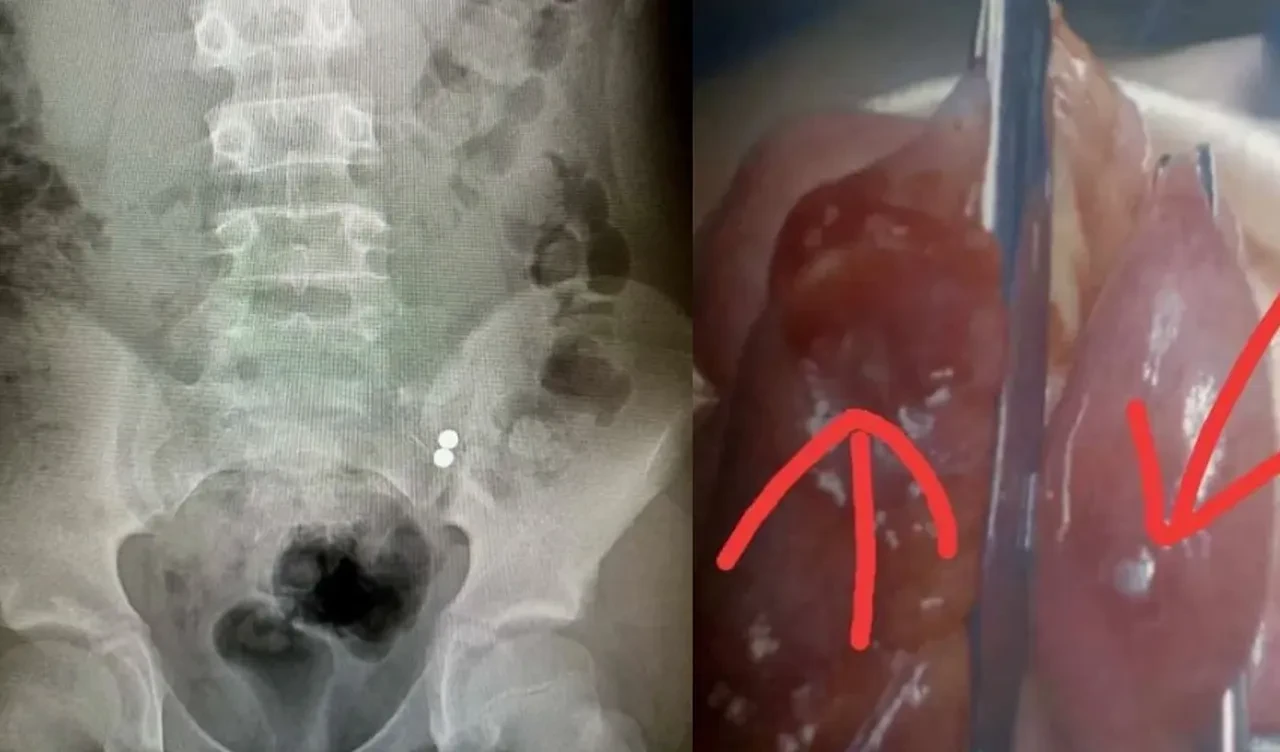

12 yaşındaki Bobby de bu akıma uymak istedi fakat küçük bir manyetik topu ağzına attı. Ancak top çok küçük olduğu için direkt boğazından aşağı kaydı. Hastaneye gittiğimizde röntgen çekildi ve biri göğsünde, diğeri bağırsağında olmak üzere iki top olduğu ortaya çıktı.

Doktorlar manyetik topların Bobby'nin iç organlarına zarar vereceği endişesiyle acil olarak ameliyata aldılar. Ameliyat 3 saat sürdü. Bobby'nin annesi Hannah, "Eğer birkaç saat daha bekleseydik, bağırsakları delinecek ve stoma torbası kullanmak zorunda kalacaktı." diyerek tehlikenin boyutunu gözler önüne serdi.